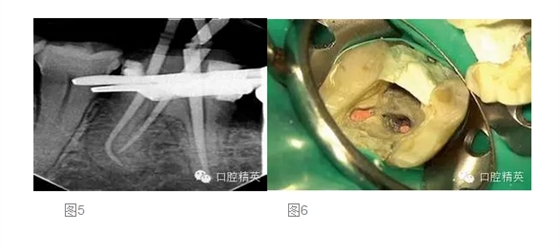

在第二次就診時,我們再次進(jìn)行抗菌的根管沖洗,然后使用消毒的紙尖擦干根管。將牙膠尖置于根管內(nèi),拍攝主尖片(圖 5)。根充糊劑為AHPlus(DENTSPLY DeTrey)。根管充填過程中,使用System B及連續(xù)波加壓技術(shù)對根尖4mm進(jìn)行根管充填,回填過程使用Obtura III Max 的熱塑牙膠(Obtura Spartan)。

在根管充填過程中,要非常小心不要將根充糊劑壓入根管側(cè)穿的部位。對近中舌根的回填置于穿孔的根尖方向(圖 6)。根管充填后,使用MTA 輸送器(同樣也是DENTSPLY Maillefer 公司)對側(cè)穿部位進(jìn)行MTA修補,封閉穿孔的部位。正如轉(zhuǎn)診醫(yī)生所要求的,遠(yuǎn)中根管內(nèi)為預(yù)留樁的空間,轉(zhuǎn)診醫(yī)生打算自己進(jìn)行樁道預(yù)備,以放置能夠放射顯影的樹脂樁(圖 7)。使用Cavil G(3MESPE公司)作為冠部的暫封材料。最后叮囑患者復(fù)診以最終修復(fù)患牙,同時6個月后進(jìn)行復(fù)查。